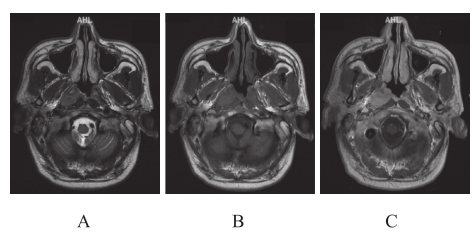

鼻咽癌在T1加权图像(T1-weighted imaging,T1WI)呈中等、较低信号,而在T2加权图像(T2-weighte d imaging,T2WI)呈中等偏高信号;注射造影剂后的T1WI图像可见病灶实质部分明显强化。部分肿瘤的边缘较清楚,可呈肿块样突入鼻咽腔,或向黏膜下生长突入咽旁间隙的内后方;大部分病灶呈浸润性生长,此时肿瘤多与周围结构分界不清,脂肪间隔模糊、消失(图2-3-2)。鼻咽癌周围结构受侵的MRI表现,见表2-3-1。

图2-3-2 鼻咽癌MRI表现

A—T2WI平扫;B—T1WI平扫;C—T1WI增强扫描。